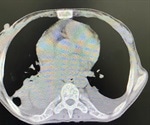

Overlap syndrome, or COLDOSA, is the name given when a patient is suffering from both chronic obstructive pulmonary disease and obstructive sleep apnoea. Combined, these conditions cause a significant drop in oxygen during sleep, leading to an increased risk of disability and death.

Mediastinal infections are primarily related to surgery, perforation of the esophagus and infectious spread from adjacent regions.